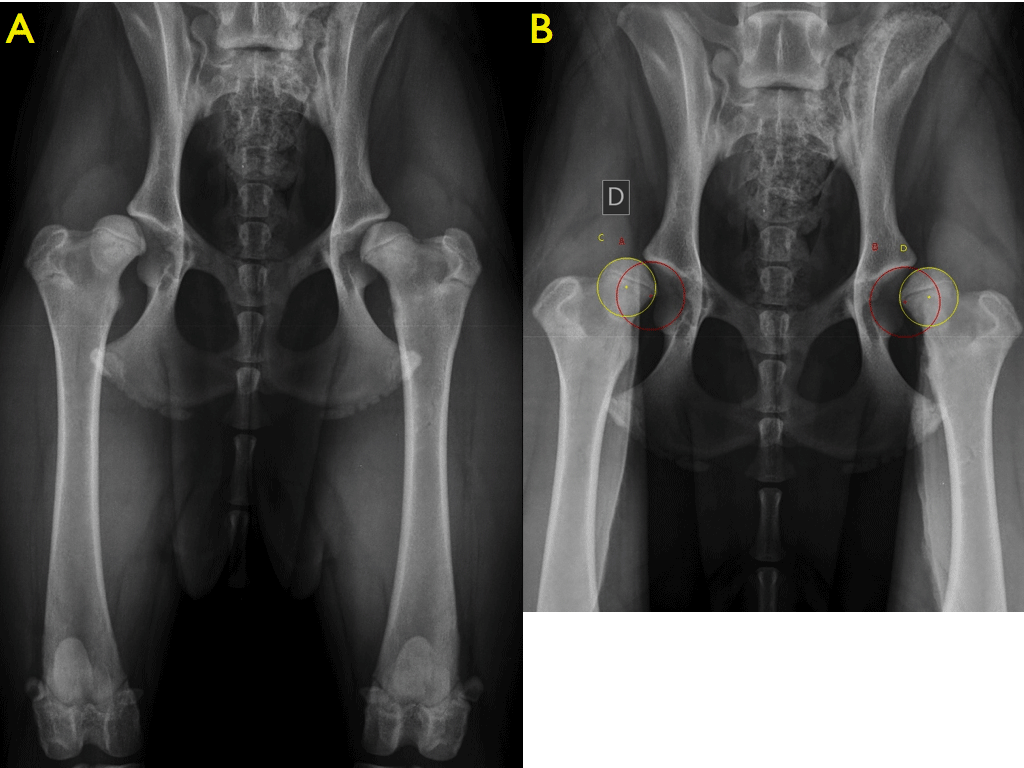

Questa patologia non è diagnosticabile alla nascita poiché compare solo con lo sviluppo dell’articolazione. Durante la crescita del cucciolo, nei primi mesi di vita, può essere diagnosticata con uno studio radiografico del bacino in 4 proiezioni (diagnosi precoce a 4-5 mesi). L’esenzione da displasia dell’anca invece può essere accertata solo dopo il completamento dello sviluppo scheletrico mediante l’esecuzione di radiografie ufficiali. http://www.fsa-vet.it/

A) proiezione ventro-dorsale anche estese B) proiezione ventro-dorsale anche in distrazione

La diagnosi precoce di questa patologia può essere effettuata a tre e mezzo/ quattro mesi di vita, attraverso una visita ortopedica ed uno screening radiografico, in una fase in cui i sintomi clinici possono essere ancora assenti o “sfumati” (infatti una cane di 3 – 4 mesi di età spesso non manifesta dei sintomi clinici di displasia, anche se gravemente affetto, sia per il ridotto peso corporeo, sia per la capacità della cartilagine articolare di sopportare gli insulti iniziali).

C) ventro-dorsale a rana D) DAR bordo acetabolare dorsale